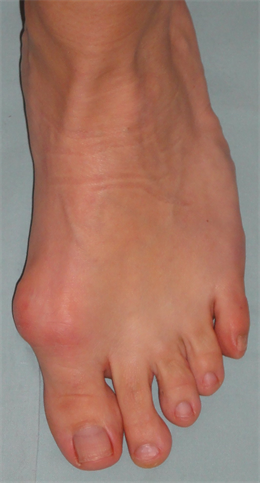

Figure 4. Patient Nr. 1: Recurrance of preoperated hallux valgus and hammertoe II.

Figure 5. Patient Nr. 1. Correction of a pathological DMAA without loss of length. Distal fragment has only a point contact to the proximal bone partner. Additional Akin osteotomy and PIP arthrodesis and FDL tranfer on the 2nd toe.

Figure 6. Patient Nr. 1. After 6 months the bone healing is completed with no loss of correction. Immediate full weigh bearing was allowed.